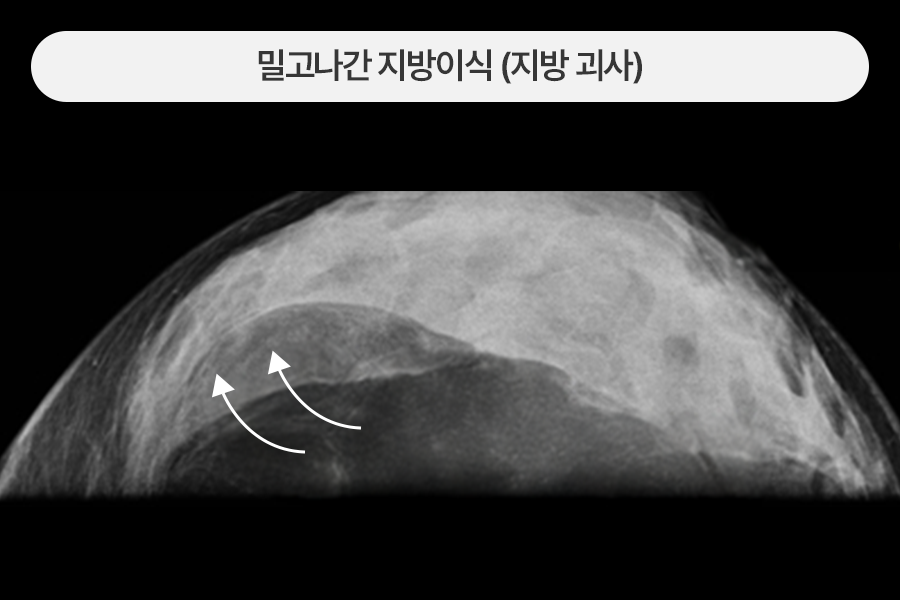

녹아 내린 지방이 유방을 가로질러 띠를 만든 경우

생착되지 못한 지방괴사 덩어리가 유방을 가로지르는 긴 띠를 만들고

내시경 소견에서도 다량의 석회화가 관찰되었습니다.

초음파와 내시경 등 영상 장치 가이드 하에 다양한 지방이식 부작용 병변들을 제거하였습니다.